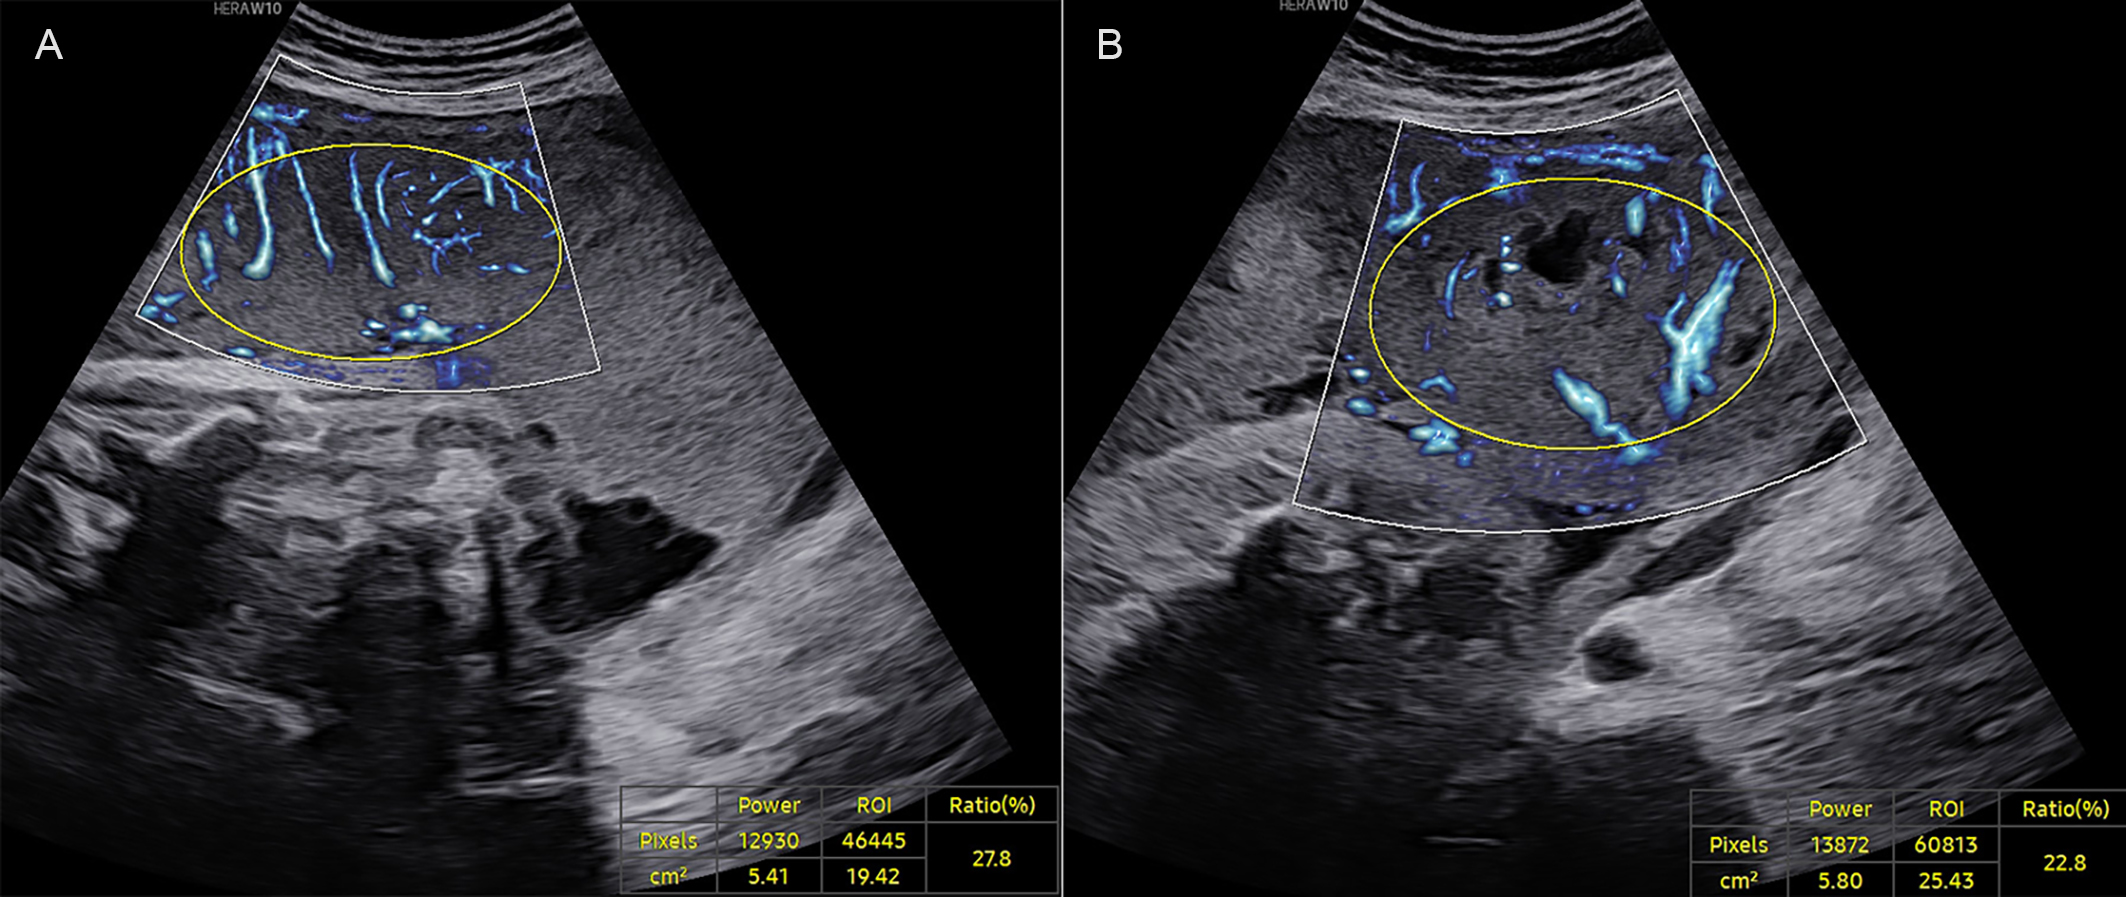

Fig. 2. A late-onset PE case at 37+0 weeks of gestation. (A) VIMV for the middle segment (VIMV-m, 27.8%). (B) VIMV for the peripheral segment (VIMV-p, 22.8%). The yellow circle shows the ellipse-shaped region of interest for which the VIMV was calculated.